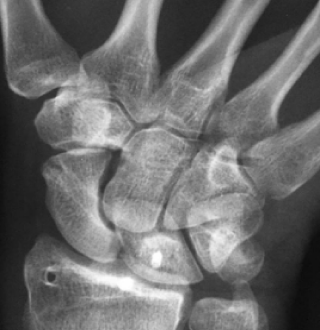

주상월상인대파열 진단법

X-ray 진단으로 보이지 않을 경우

→ 초음파, MRI 영상 검사

힘주지 않았을 때 우측

힘주지 않았을 때 좌측